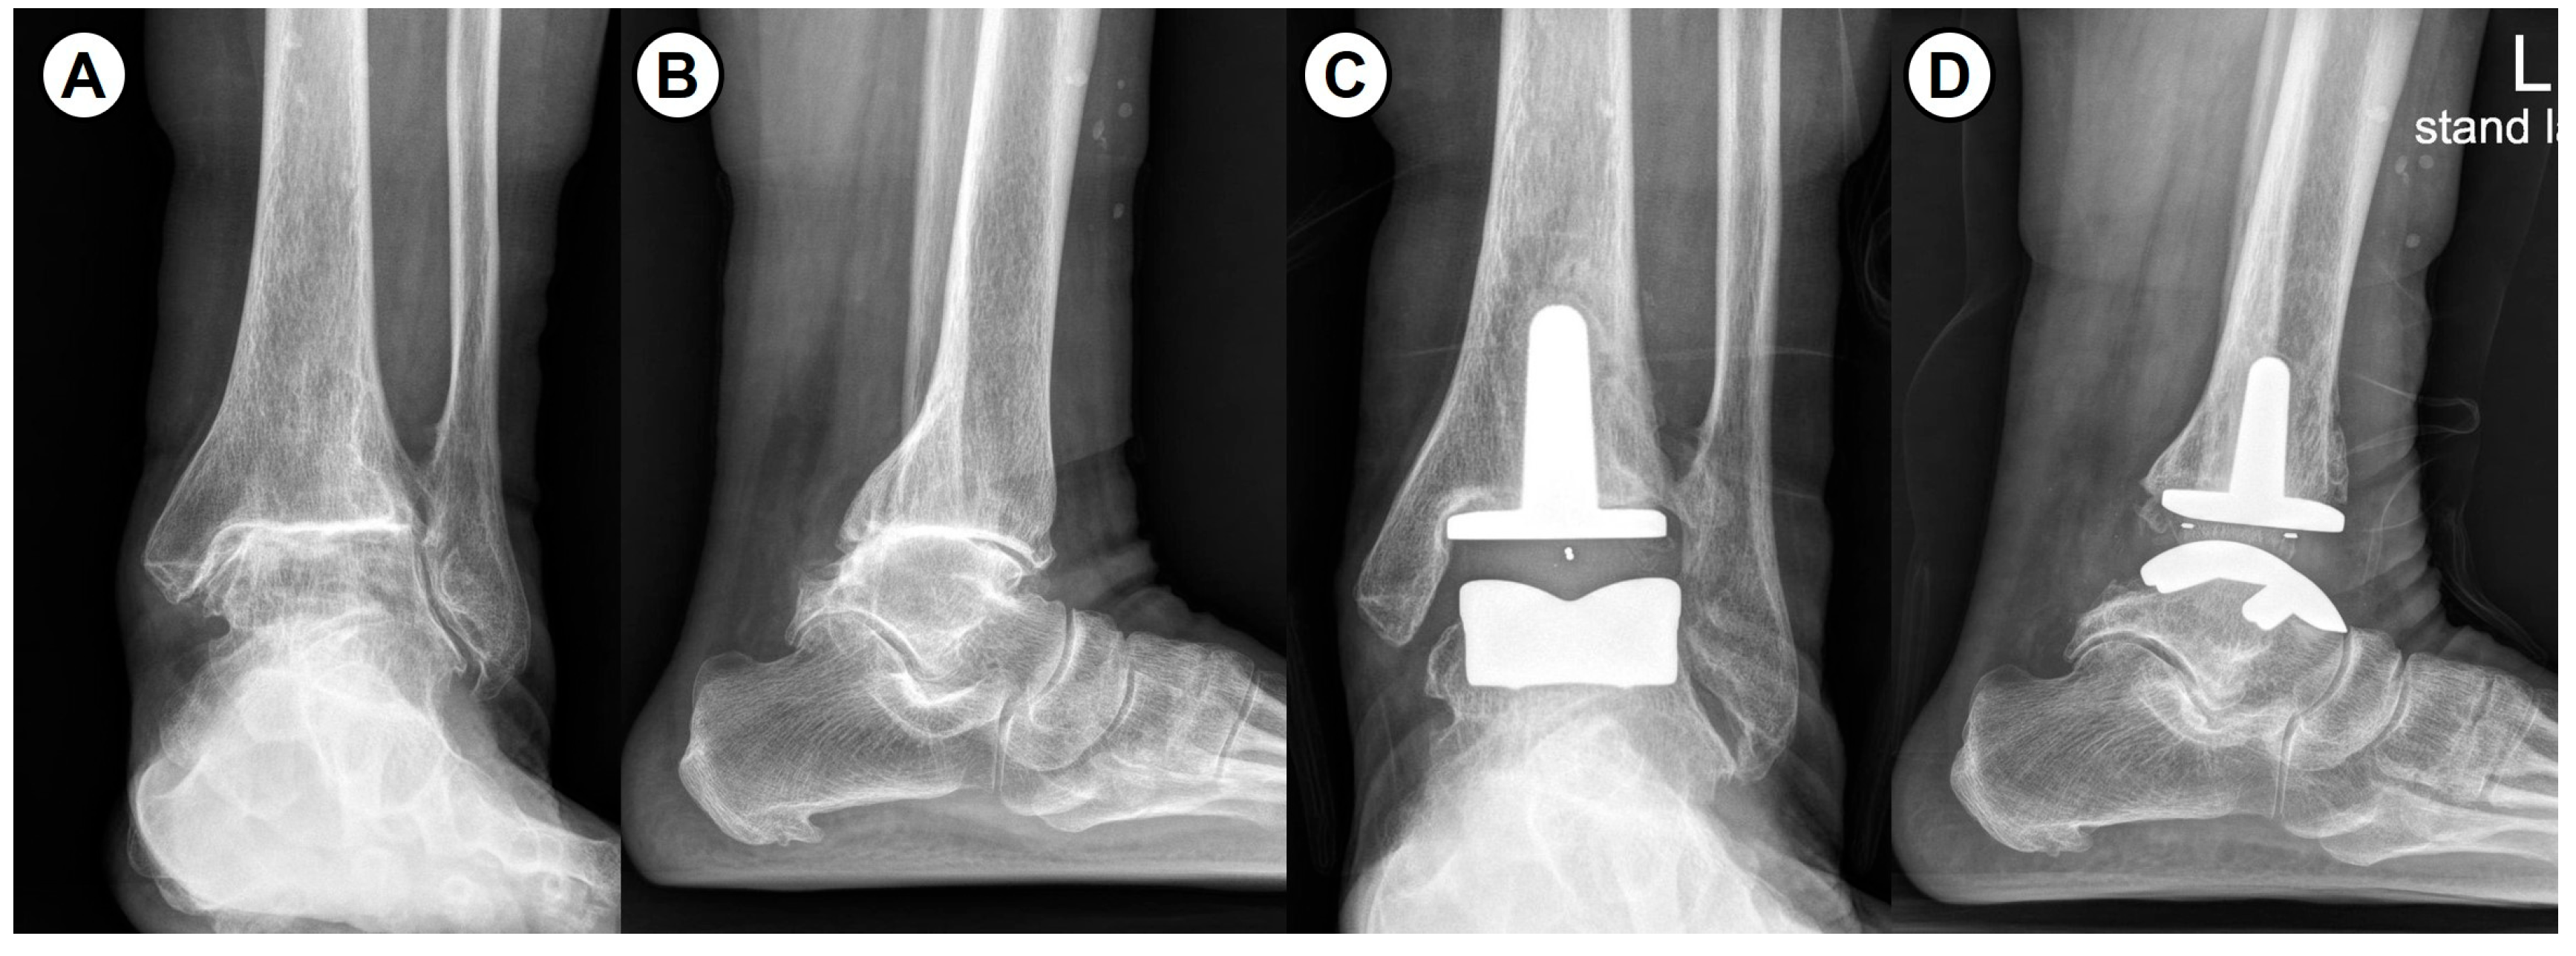

- Jeong, B.O.; Jung, H. Severe ankle osteoarthritis: Treatment with total ankle arthroplasty. J. Korean Foot Ankle Soc. 2018, 22, 8–15. [Google Scholar] [CrossRef][Green Version]